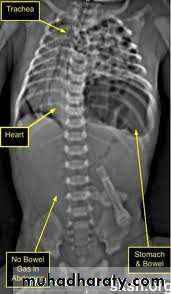

Congenital Diaphragmatic Hernia

Bochdalek Herniapostrolateral Morgagni Hernia

80-90% Lt. side 2-6%

Pathophysiology:- Pulmonary hypoplasia.- Pulmonary hypertension- Persistent fetal circulation

O/E:• Scaphoid abdomen.• Increased antero-posterior diameter of the chest.• Decreased air entry on the affected side with decreased tidal volume.• Bowel sound may be heard in the chest.• Shifting of cardiac impulse to the right.

Diagnosis:-- CXRo Air & fluid filled loops of bowel in the chest.o Paucity of intestinal gas in the abdomen.o Mediastinal shift (heart shifted to the right).o Tip of NG tube seen in the chest.